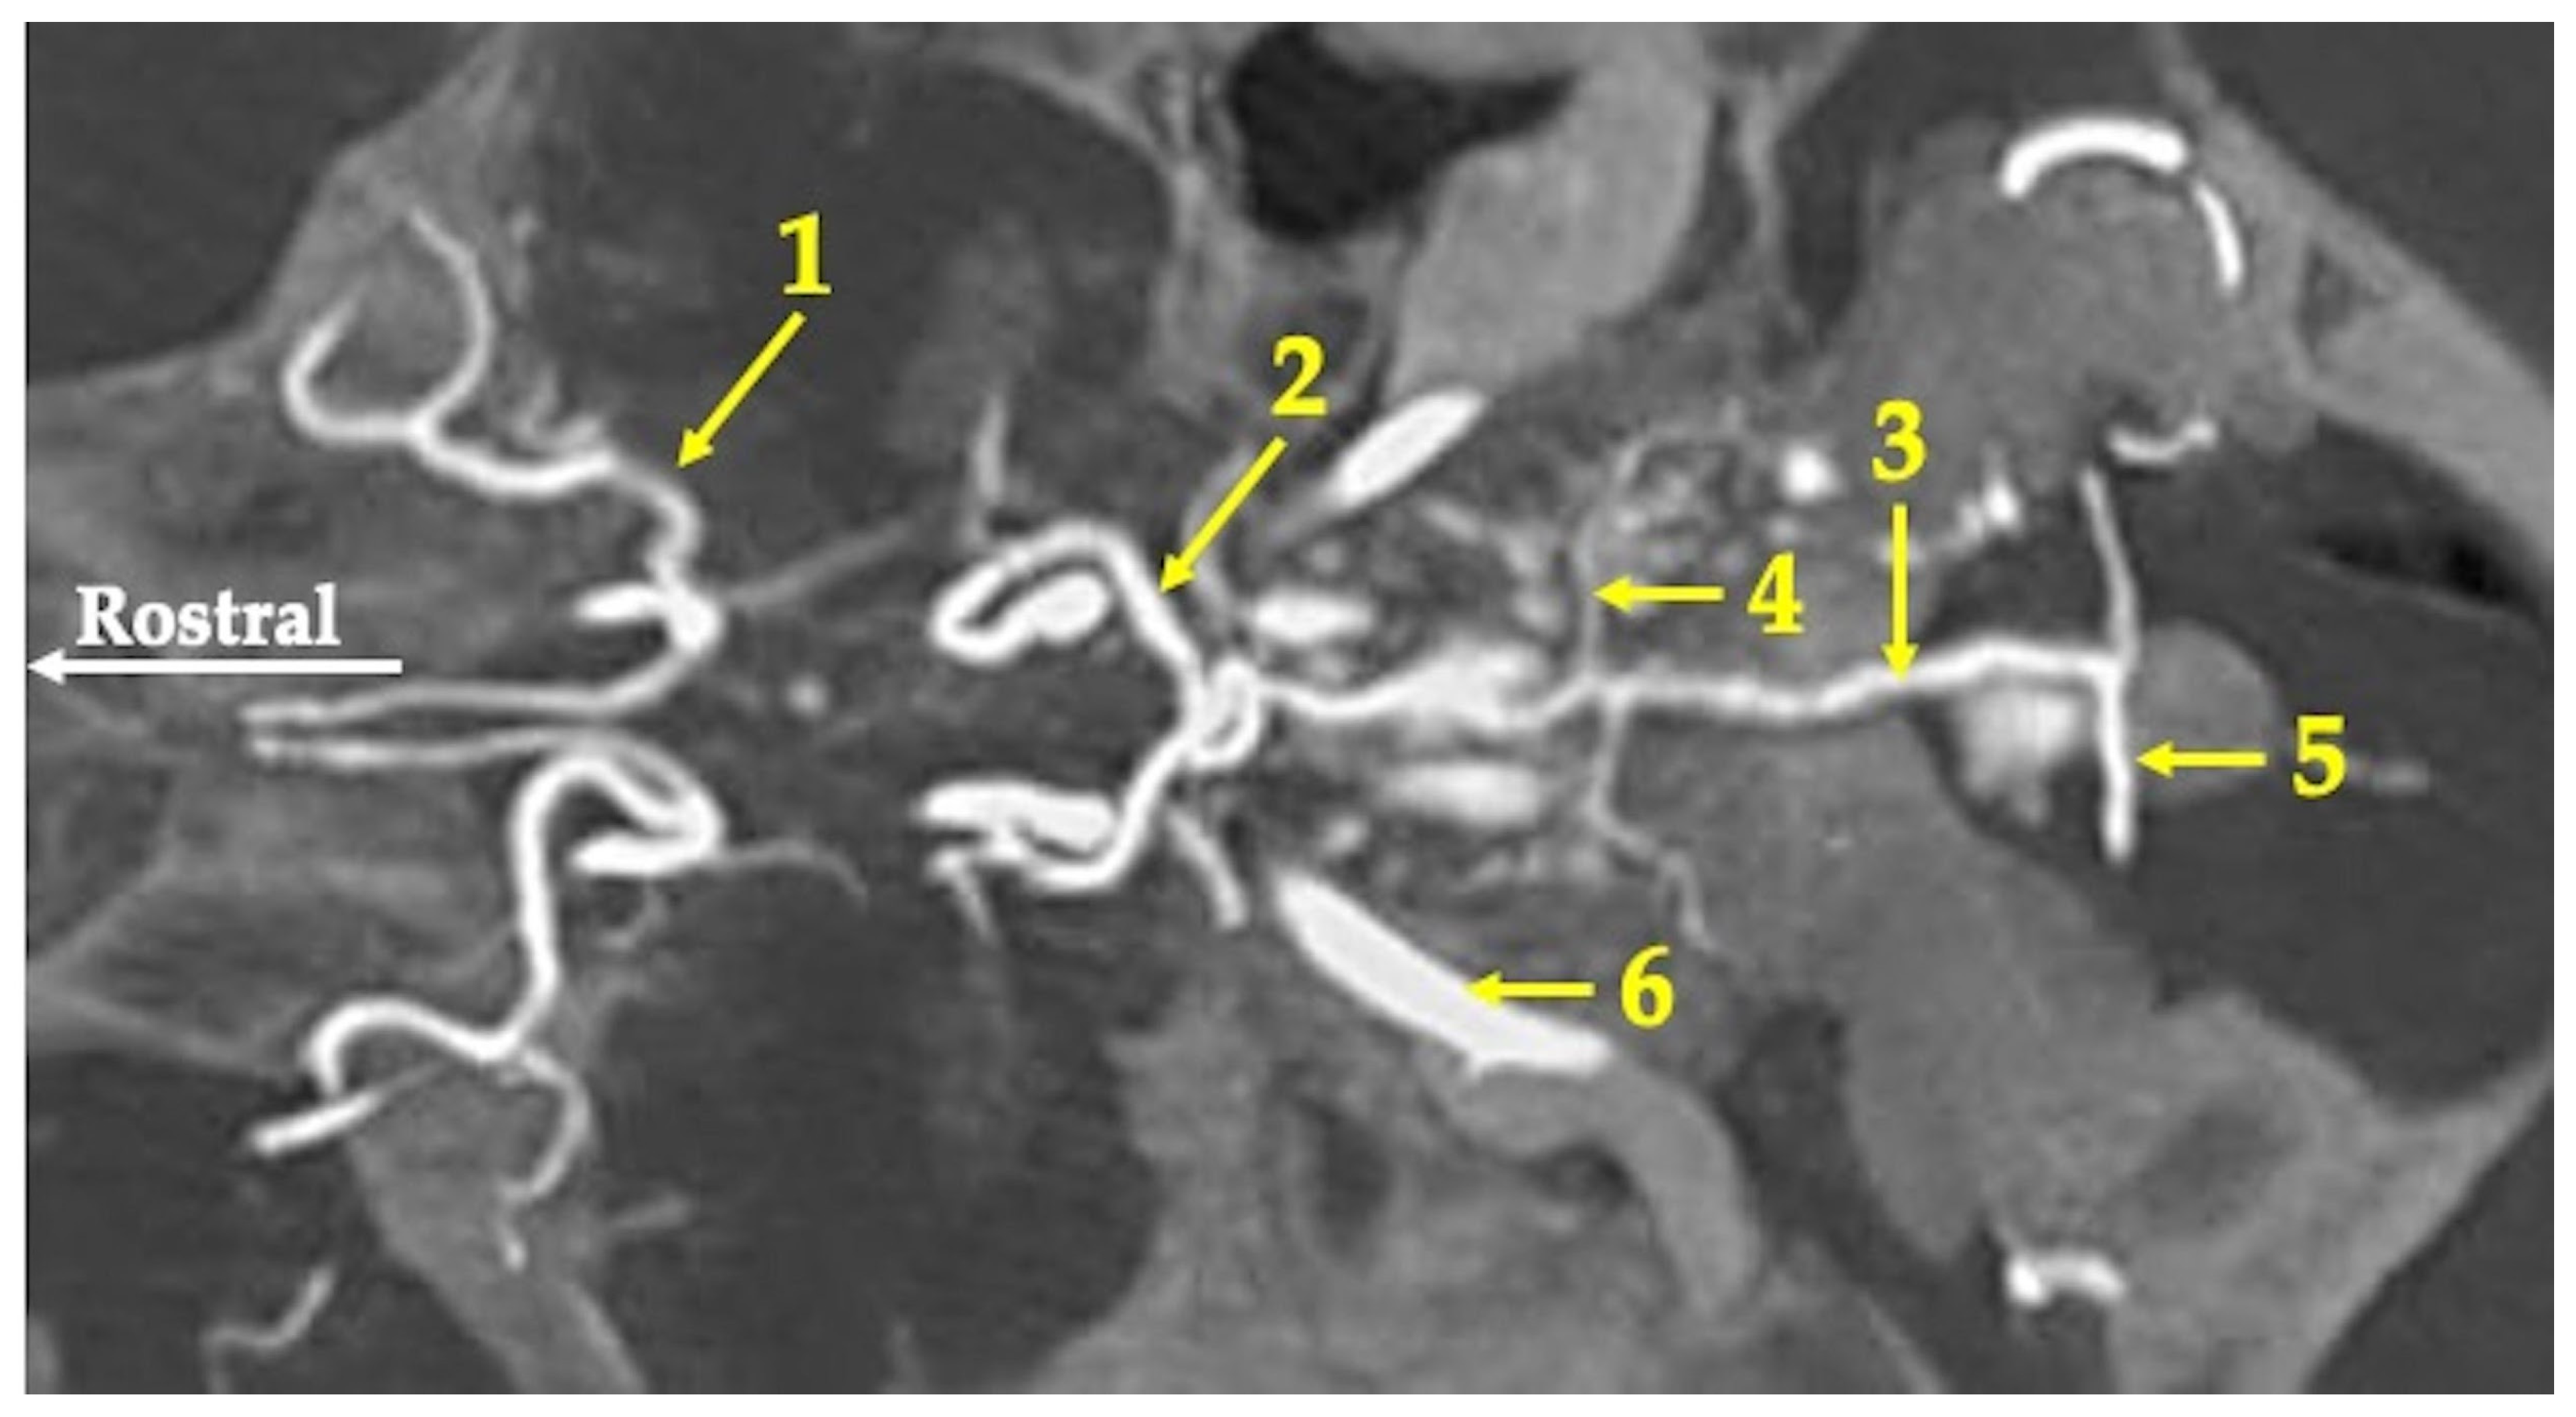

3. Results